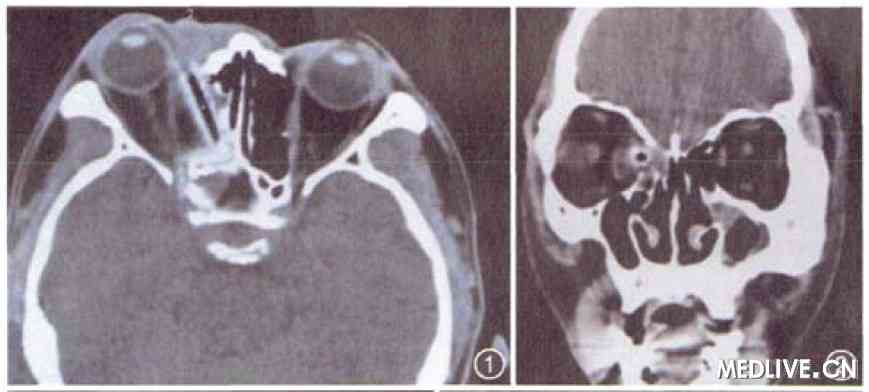

辅助检查:眼眶CT扫描(图1,2):右侧眶内壁向内移位,可见长约3 cm的管状异物影(其外部高密度区CT值为121 Hu,内部低密度区为-238 Hu)穿过筛窦进入后组蝶窦,异物前部达眶上裂。

图1 右眼眶内植物性异物患者CT水平位扫描,显示右侧眶内壁向内移位,可见长约3 cm的管状异物影(其外部高密度区CT值为121 Hu。内部低密度区为-238 Hu)穿过筛窦进入后组蝶窦,异物前部达眶上裂

图2 右眼眶内植物性异物患者CT冠状位扫描,显示异物呈空管状

本例行CT检查时已近20 d,属亚急性期,表现为中央为类空气样低密度影,外周为较眼外肌密度高的管状影像。结合术后测量异物长度、直径与CT测量对照,认为低密度影为树枝的中央疏松部分,周围管状高密度影为树枝的周围密质部分,而不是所谓的机化炎性软组织,与国内文献关于亚急性期的报道不相符。本例异物为柳枝,其外层为树皮,结构较为疏松,内层主干结构较为致密,体液及炎症反应物先浸润疏松的树皮及表层树干,使之表现为高密度影,而内部由于尚未完全被浸入,所以仍为低密度影,其内外密度的差异,导致了管状异物影的出现,为此例的典型影像。